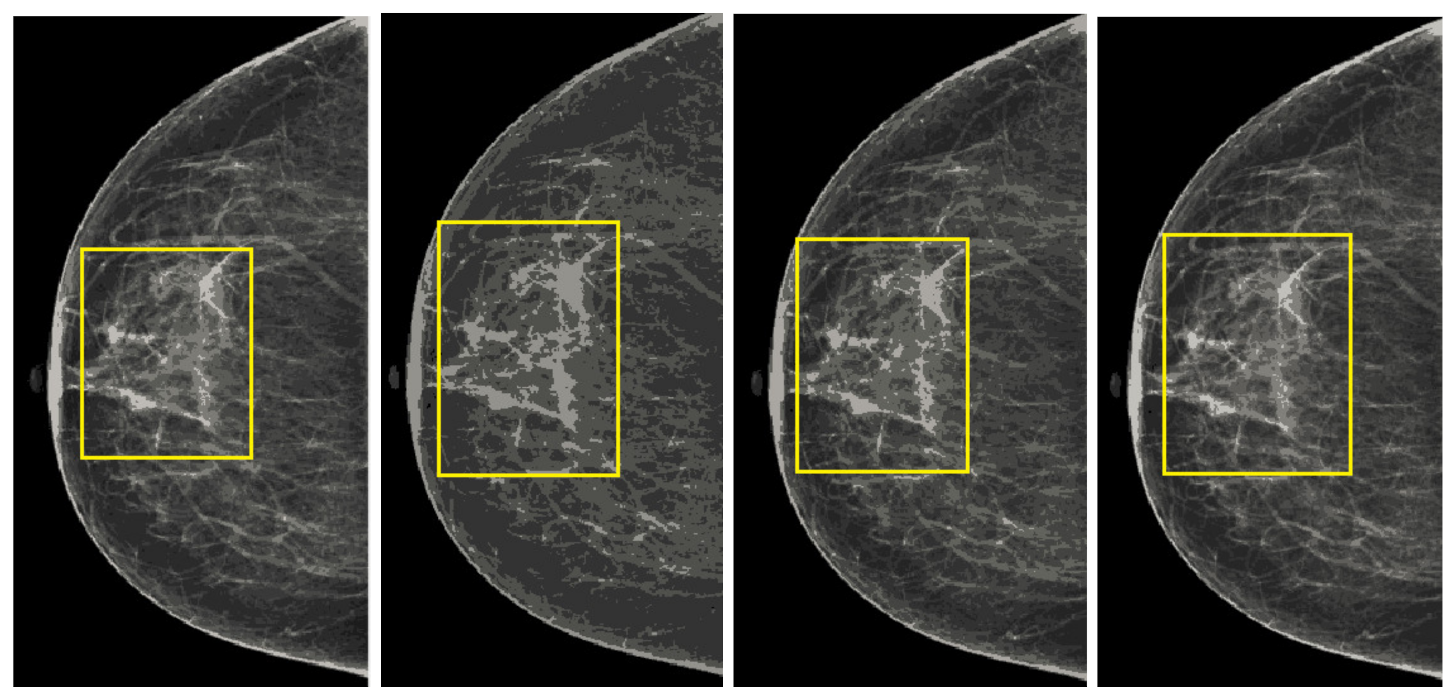

5.1. Analysis of Proposed Image Enhancement Technique

We also measured the PSNR, the image contrast, and the EME of each category of databases, as we analyzed the image in terms of visual observation. The Table 3 shows the performance of our proposed image enhancement method. It can be seen from the Table 3 that our proposed method improved PSNR, contrast, and EME, and this also shows that our method can work on every category of BI-RADS. Because many techniques do not work on higher grade BI-RADS due to the complexity and the images are not of good quality. We obtained an average improvement in PSNR, contrast, and EME in the Table 4. For more observations, we analyzed the visual image of each category and we analyzed the CC and MLO of each category as shown in the Figure 7, Figure 8, Figure 9, Figure 10, Figure 11, Figure 12, Figure 13, Figure 14, Figure 15 and Figure 16. From the figures, every detail of image of every category can be observed, leading to better segmentation of the abnormal region. This image enhancement technique can be used as preprocessing steps for the detection of breast cancer. It is a very fast processing algorithm and it takes on 21.13 s. It gives opportunity to medical experts to analyze the mammogram images very quickly to propose the timely treatment.

Figure 7.

Analysis of CC view of BI-RADS-1 mammogram images.

Figure 8.

Analysis of MLO view of BI-RADS-1 mammogram images.

Figure 9.

Analysis of CC view of BI-RADS-2 mammogram images.

Figure 10.

Analysis of MLO view of BI-RADS-2 mammogram images.

Figure 11.

Analysis of CC view of BI-RADS-3 mammogram images.

Figure 12.

Analysis of MLO view of BI-RADS-3 mammogram images.

Figure 13.

Analysis of CC view of BI-RADS-4 mammogram images.

Figure 14.

Analysis of MLO view of BI-RADS-4 mammogram images.

Figure 15.

Analysis of CC view of BI-RADS-5 mammogram images.

Figure 16.

Analysis of MLO view of BI-RADS-5 mammogram images.